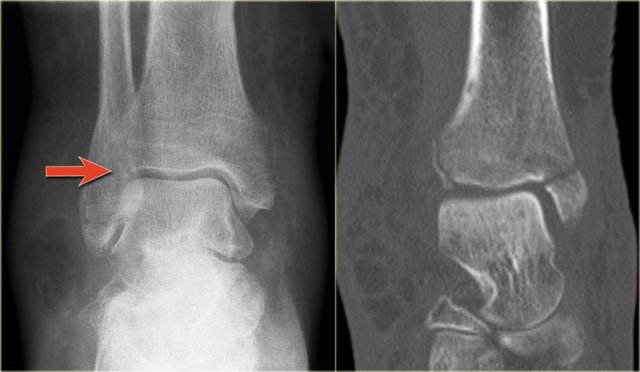

In some cases a fracture of the posterior malleolus is barely or not visible on the radiographs and can only be seen on CT.

First study the radiographs and then continue with the CT.

By the way....there are two fractures.

You can enlarge the images by clicking on them.

The CT shows an avulsion of the tertius at the insertion of the posterior syndesmosis (red arrows).

The alignment is so perfect, that you do not see the fracture on the radiographs.

Maybe the fracture is seen on the AP-view as indicated by the red arrows, but this is questionable.

Notice that there is also an avulsion at the tibial insertion of the anterior syndesmosis, i.e. Tillaux fracture.

This combination of findings implicate that the ankle is unstable.

A syndesmotic screw has to be inserted.